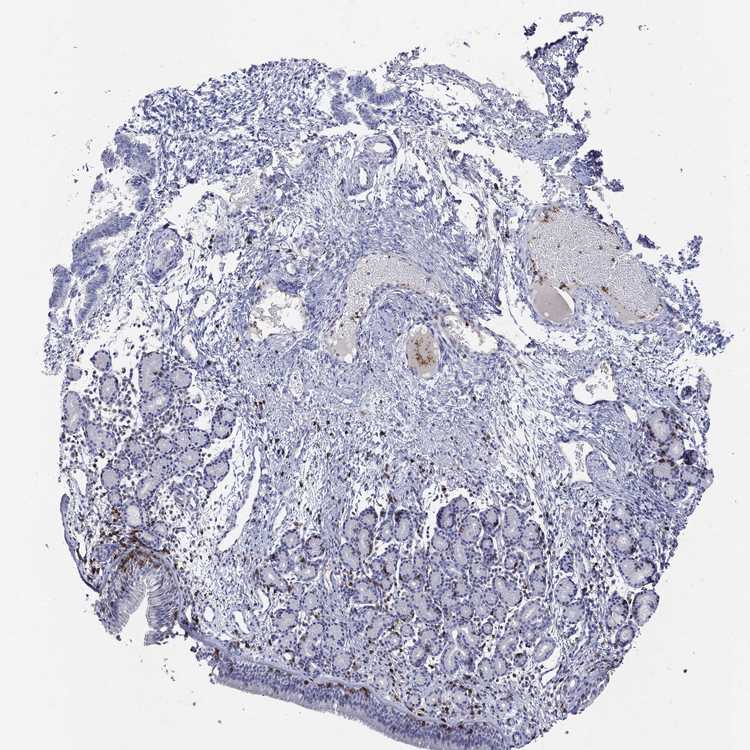

TISSUE PRIMARY DATA NASOPHARYNX Show tissue menu

NASOPHARYNX - Antibody stainingi

Antibody staining in the annotated cell types in the current human tissue is reported as not detected, low, medium, or high, based on conventional immunohistochemistry profiling in selected tissues. This score is based on the combination of the staining intensity and fraction of stained cells.

Each image is clickable and will lead to virtual microscopy that enables deeper exploration of all samples and also displays staining intensity scores, fraction scores and subcellular localization as well as patient and tissue information for each sample.

Antibody HPA011157Antibody CAB002223Antibody CAB012978Antibody CAB079960

Respiratory epithelial cells Not detectedNot detectedNot detectedNot detected